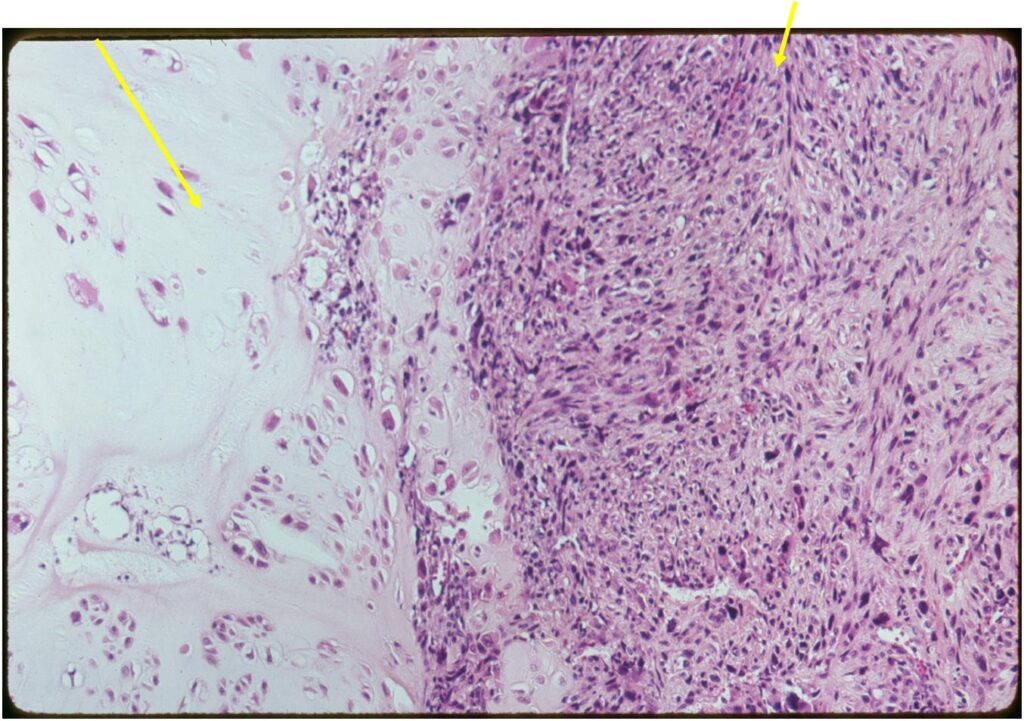

Junction of cartilaginous and noncartilaginous components is sharp and distinct. There are no dedifferentiated areas admixed in the middle of the cartilaginous areas

(Right Arrow) Dedifferentiated Component

- Chondrosarcoma component is often grade I (Low Grade Hyaline Type Cartilage)

- Dedifferentiated component

- Predominant noncartilaginous/spindle sarcoma component varies

- Fibrosarcoma and MFH most frequently reported

- MFH is a high grade pleomorphic spindle cell tumor with a storiform pattern